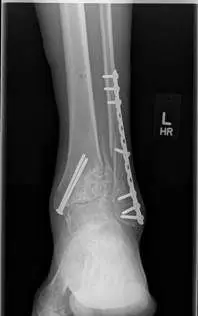

The following are images after surgical replacement of the ankle joint with a mobile bearing ankle prosthetic called the S.T.A.R. (SBI). This replacement joint will function similarly to a normal anatomical joint, allowing the patient normal function in daily activities, but was not designed to take repetitive use during more intense athletic activity. The joint has a polyethylene spacer between two metal parts that acts as shock absorber and gliding agent similar to cartilage. There is physical therapy that is required after surgical joint replacement in order to get the patient back to funcional capacity.

These first three pics are placement of screws in the medial malleolus and distal fibula to aid in stability.

These are final pics of the ankle replacement after fusion takedown

Preop, Intraop and Postop X-rays status post Total Ankle Replacement for Ankle Arthritis